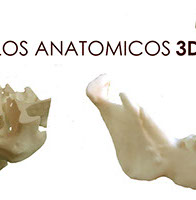

innovación dental

innovación dental